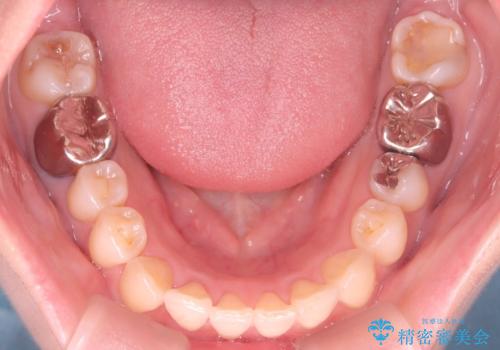

- 前歯の翼状捻転の改善を希望してこられた患者様です。

下顎の叢生はインビザラインで解決することがきましたが、上顎の捻転が完全には改善できなかったため、上顎は途中からワイヤーを用いて治療を行っています。

捻転の改善はインビザラインで苦手とするところですので、うまく治らない場合はワイヤーを提案しています。